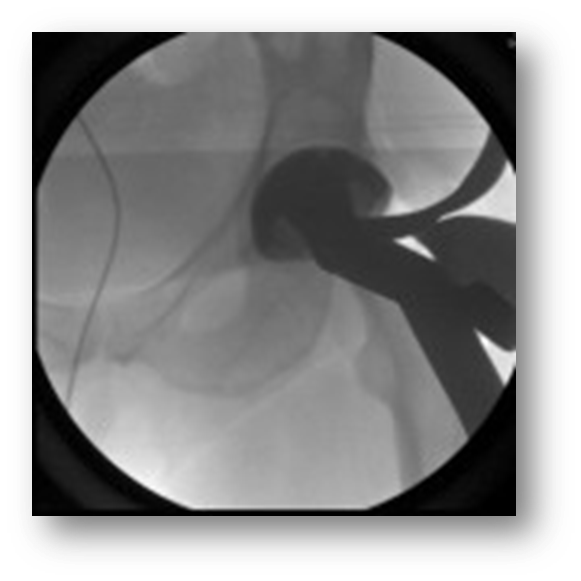

Early Laparoscopic Cholecystectomy (ELC)

•Surgical removal of the gallbladder using a tiny camera inserted through the navel for guidance (laparoscopic)

•When imaging is used during an ELC it is referred to as an Operative Cholangiogram (can also be done using the portable and a detector)

ELC

•The surgeon locates the common bile duct and inserts a catheter to introduce x-ray contrast

•Move the C-Arm to directly over the patient’s gallbladder (right upper quadrant)

•The patient is supine on the table

•You will be obtaining a PA projection (tube under patient)

•Fluoro while the surgeon pushes contrast through the bile duct and biliary tree

•Send images to PACS